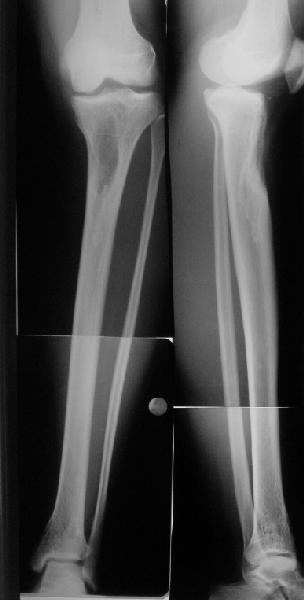

Наконец-то оперировали эту пациентку. Биопсию сделали - опухолевого ничего нет. Пока все участвовавшие в обследовании смежные специалисты и ортопеды сошлись, что это молокальная монооссальная фиброзная дисплазия.

20 марта наложили аппарат, сделали чрескожную остеотомию. К 3 апреля все докрутили. Сегодня заштифтовали. Начальные и итоговые снимки в приложении. Рекурвацию можно было еще немного больше устранить, и чуть кзади сместить диафиз. Но вроде и так ничего выглядит, по сравнению с тем, что было. Комментарии приветствуются.